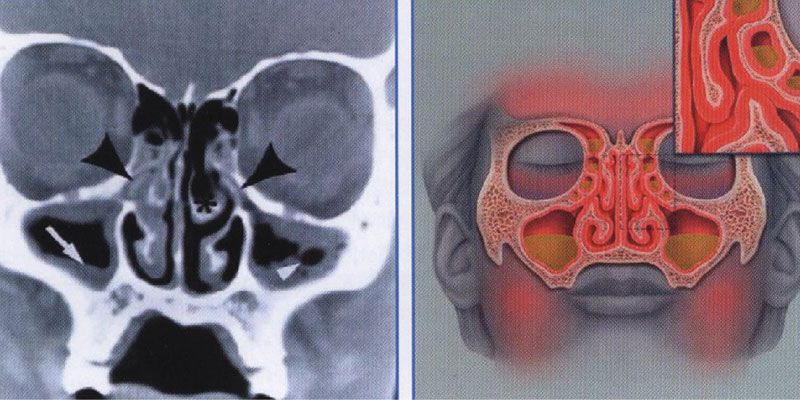

КТ-снимки хронического этмоидита: подробная визуализация

Раздел: Фотодневник открытий